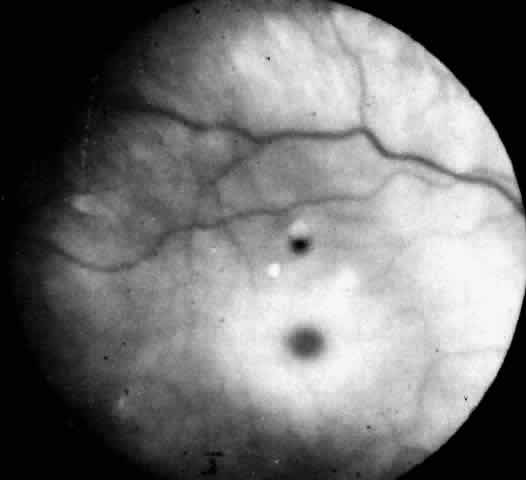

| Farber's disease is a rare autosomal recessive disease. The inborn

error is in ceramide metabolism due to lack of the enzyme acid ceramidase. The

first case of disseminated lipogranulomatosis was described

by Farher in 1949; by 1952 he had observed two additional cases.91 There are now more than 28 reported cases in the literature.92,93 CLINICAL MANIFESTATIONS. The disease begins in the first few weeks of life and presents as irritability, vomiting, hoarseness, failure to thrive, and painful swollen joints. Subcutaneous periarticular nodules develop, especially at the ankle and elbow joints. Hoarseness is severe because of progressive granulomatous infiltration of the epiglottis and larynx. Disturbance in swallowing with episodic bouts of fever and pulmonary consolidation is common. Some infants develop systolic murmurs owing to valvular involvement. Most have a generalized lymphadenopathy with occasionally moderate hepatomegaly and rarely splenomegaly. Characteristically intellect is unaffected and involvement of the nervous system is not a prominent feature.91 However, hypotonia and diminished deep tendon reflexes due to a peripheral neuropathy and anterior horn cell involvement have been reported. In such cases electromyographic studies show signs of denervation and elevated cerebrospinal fluid protein. Most children do not survive the fourth year, although a few cases of intermediate severity with longer survival have been reported.94 OCULAR MANIFESTATIONS. The retinal changes in Farber's disease are subtle and easily overlooked. The fundi of one 8-month-old patient had been examined several times following the onset of the disease at age 2 weeks and considered to be normal. Cogan and colleagues95 subsequently observed and reported a diffuse grayish opacification of the retina about the fovea, producing a mild cherry-red spot (Fig. 9). The parafoveal opacity differed from that seen in Tay-Sachs disease in that the opacity was pale gray instead of white and it was accompanied by little, if any, pallor of the optic disc. Shortly before death at age 11 months there was a suggestion of a peppery pigmentation of the entire retina and some abnormal pigmentation in the macula. The retinal vessels showed no abnormality. Visual function, as judged by the patient's attentiveness, retention of the optokinetic response, and absence of nystagmus, was normal. Zetterstrom's patient with Farber's disease had no retinopathy.96 At age 17 months he developed a xanthoma-like growth approximately the size of a rice grain in the conjunctiva over the left eye. Microscopic examination of the excised conjunctival granuloma showed a similar histologic picture to that of a subcutaneous granuloma, with groups of irregularly formed large foam cells with granular cytoplasm weakly positive in reaction to fat stains. François97 has reported central macroscopic subepithelial corneal opacities in two children with Farber's disease. NEUROPATHOLOGY. The characteristic pathologic lesion in Farber's disease is a granuloma containing foam cells filled with PAS positive material extractable with lipid solvents. Ultrastructural examination of these cells has shown cytoplasmic vacuoles limited by a single membrane and containing comma-shaped tubular structures. The vacuoles are acid phosphatase positive and probably represent lysosomes. They are called Farber bodies. Elevated levels of ceramide have been found in subcutaneous nodules in the liver, kidney, brain, and lungs. In the brain, neurons and glial cells are distended owing to the accumulation of ceramide and gangliosides. Routine sections of the paraffin-embedded eye tissue show no histologic abnormalities in Farber's disease, but frozen, unstained sections show birefringent lipid crystals in the ganglion cells of the retina. The accumulation of lipid is most conspicuous in the parafoveal region of the macula where the ganglion cells are abundant. In spite of their distention, the engorged cells remain intact and there are no extracellular deposits of lipid in the retina. The optic nerve is not atrophic.95Cogan and colleagues95 performed solubility studies in several of the organic solvents and determined that the intracellular deposit in the ganglion cells was likely to be a complex lipid rather than neutral fat or cholesterol. DIAGNOSTIC TESTS. The isolation of excess ceramide in biopsied tissue is no longer required to confirm the diagnosis of Farber's disease.98 Determination of ceramidase levels in leukocytes and cultured fibroblasts is the diagnostic procedure. The assay shows low to absent enzyme activity. Carriers are identified by demonstration of half normal levels of enzyme activity in cultured fibroblasts. Prenatal diagnosis has been accomplished in four pregnancies at risk by assaying cultured amniocytes .99 |